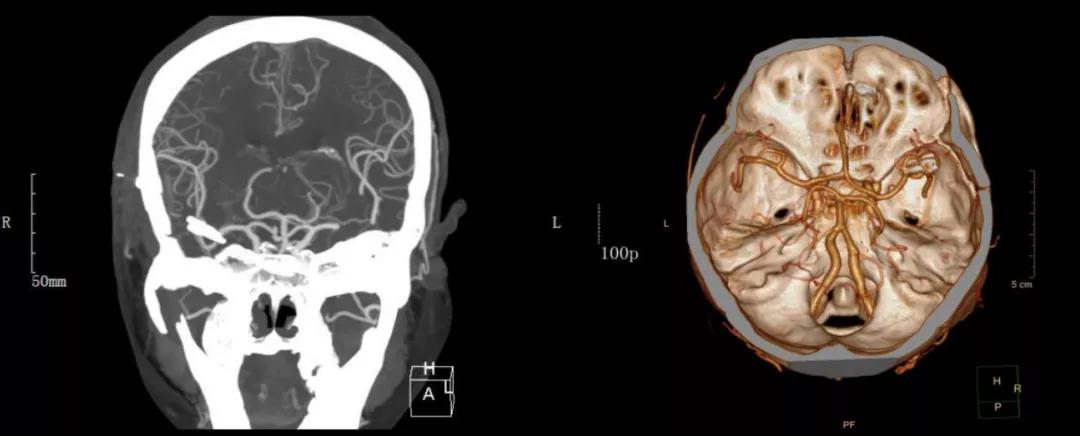

49岁的包女士(化名),因“突发头痛伴呕吐6小时”紧急送往西安医学院第二附属神经外科,入院急诊行头颅CT检查提示蛛网膜下腔出血,进一步做头颅CTA检查,确定为右侧大脑中动脉瘤破裂出血所致。

术前影像学资料: